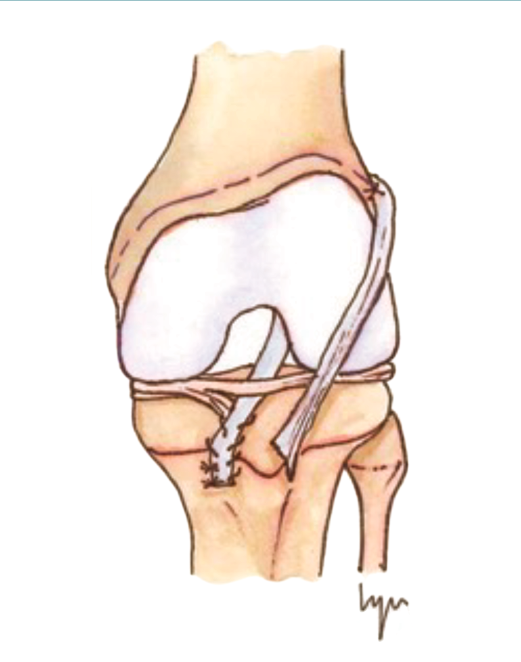

Las técnicas de “ahorro fisario” o physeal sparing

Figura 3. Técnica de la banda iliotibial.

Estas técnicas evitan la agresión de la placa fisaria. Una de las primeras fue descrita por MacIntosh y Darby(11), y modificada posteriormente por Micheli(68), conocida como la técnica de la “cintilla iliotibial” (illiotibial band –ITB–). Utiliza parte de la cintilla iliotibial como autoinjerto, dejando su porción distal unida al tubérculo de Gerdy. Es una técnica no anatómica, extra-intraarticular, en la que el injerto se pasa alrededor y por detrás del cóndilo femoral externo, en la posición over-the-top, a través de la escotadura y, posteriormente, por debajo del ligamento intermeniscal para, finalmente, fijarlo en el periostio de la tibia distal a la fisis.

Figura 4. Técnica transepifisaria o todo epifisaria.

Kocher et al.(14) publicaron buenos resultados funcionales en un grupo de 44 pacientes en estadios I-II de Tanner, sin observar deformidades ni dismetrías y con una tasa de revisión del 4,5%.

Willmiton et al.(69) también obtuvieron buenos resultados funcionales y una baja tasa de revisiones.

Desde el punto de vista biomecánico, esta técnica proporciona una mejor estabilidad anteroposterior y rotacional en comparación con las técnicas de reconstrucción “todo epifisaria” y “transtibial over-the-top”, aunque se ha observado que puede aumentar la constricción del compartimento externo con la rotación en ciertos grados de flexión(70)(Figura 3).